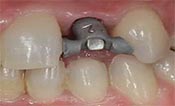

安卓健临床案例分享

安卓健种植产品销往全球100多个国家精密工程CFDA

权威认证,可放心使用。安卓健种植体手术程序简单,

更少创伤,更快恢复,更加安心。